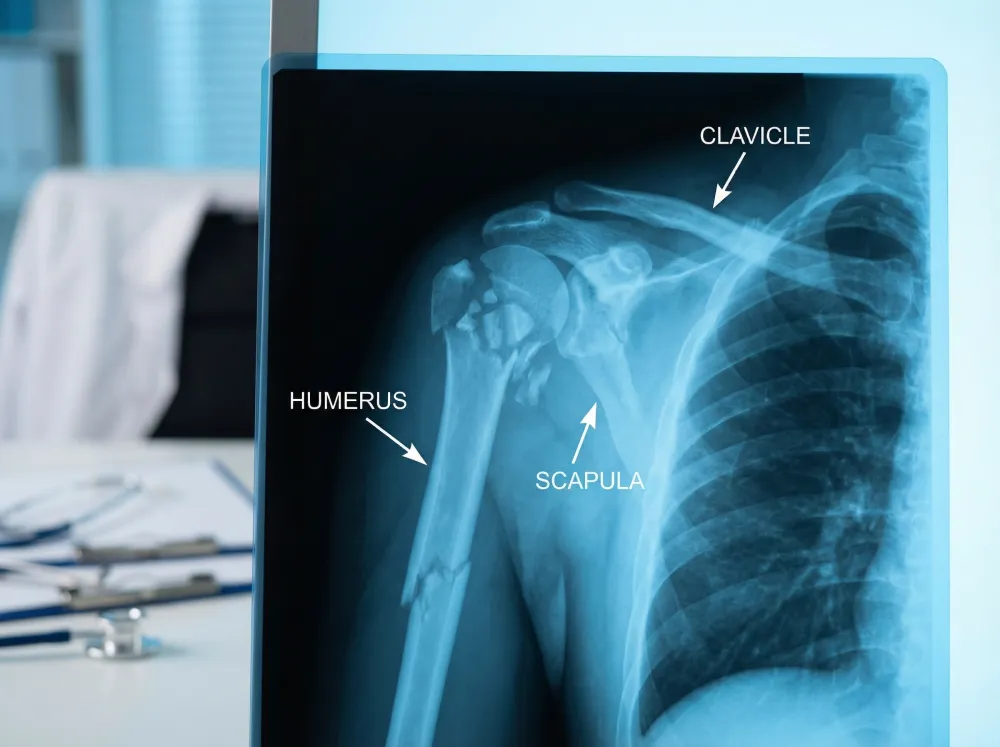

This innovative surgical technique is often utilized when a patient has a completely torn rotator cuff or severe arthritis accompanied by rotator cuff weakness. Unlike a traditional shoulder replacement, where the plastic cup is fitted into the shoulder socket and the metal ball is attached to the top of the upper arm bone, a reverse replacement switches this arrangement entirely. The metal ball is fixed to the socket, and the plastic cup is attached to the upper end of the humerus. This configuration allows the patient to use the deltoid muscle, rather than the torn rotator cuff, to lift the arm, which is particularly beneficial for older patients.